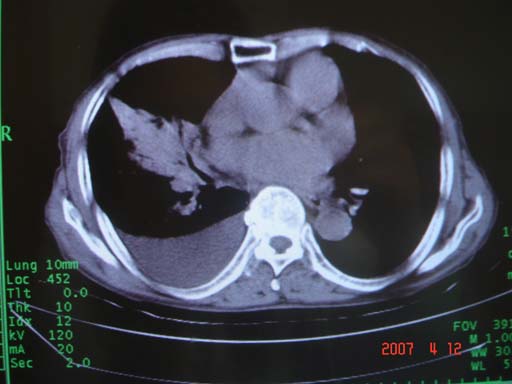

帮我 看看。男77岁咳嗽咯血2月发热2周!病人一般情况可 口痰为鲜红,有点象洗肉水(我看见他吐的痰了)

为何只有这么几幅图像?连纵隔窗都没有。但我发现上叶支气管显示不清,再加上年纪大,咯血等症状,恶性肿瘤首先得考虑。

考虑右肺新生物伴右中上肺阻塞性肺炎及含气不良,右侧胸腔积液。建议痰与纤支镜检查

考虑右侧中央型肺癌伴中上肺阻塞性肺炎、不张,胸腔积液。,建议支纤镜检查。

考虑:右上肺癌伴中上叶炎症,右侧胸腔积液。

图片不太全

根据患者老年男性,右肺上叶支气管狭窄、阻塞,伴阻塞性肺炎,考虑中心型肺癌可能性大。建议支气管镜检查

病灶局限在右肺中上叶,呈大片状实变影,内见空气支气管征,支气管分支较柔软,纵隔内未见肿大淋巴结.支持:感染性病变_1 大叶性肺炎.2 干酪性肺炎.

优先考虑右上肺干酪性肺炎并同侧中叶播散、胸腔积液。分析:右膈肌未见升高、纵隔未见明显右移,胸部各组淋巴结未见可疑肿大,中叶可见支气管铸形,肺野、肺门未见可确定肿块。

右肺上叶后段支气管中断,首先考虑中央型肺癌并右肺不张及纵隔淋巴结转移,右侧胸腔积液。